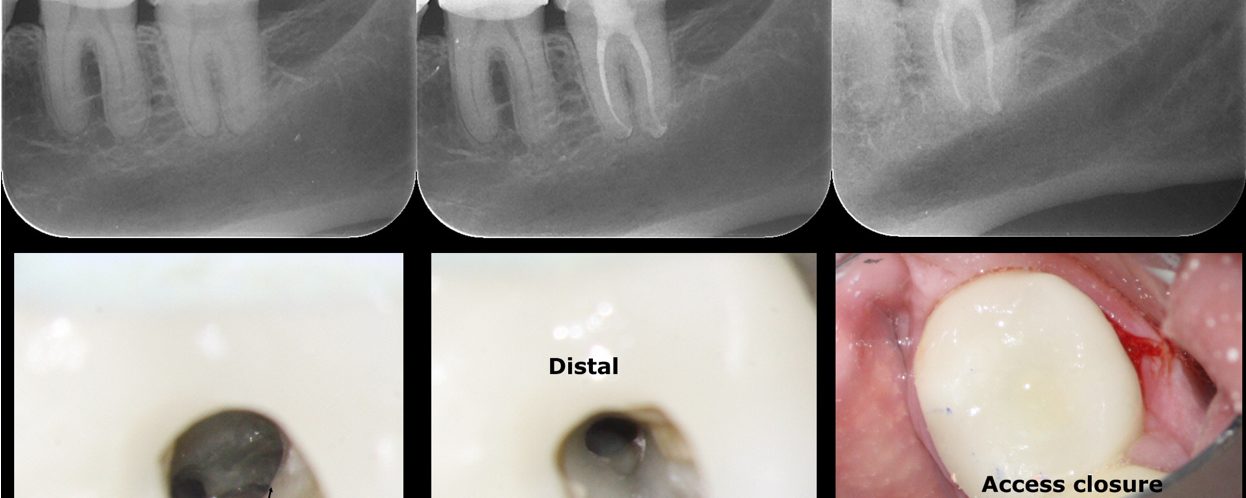

#13 – Caries Driven Access

– Sub-gingival caries distal to an isolated #13 – Gingivectomy and isolation done – Caries driven access through the distal (missing #12 and #14 made this approach possible) – No post-endodontic restoration planned as the patient is a partial denture user (maxillary an mandibular) an I don’t think she will generate enough functional load for […]